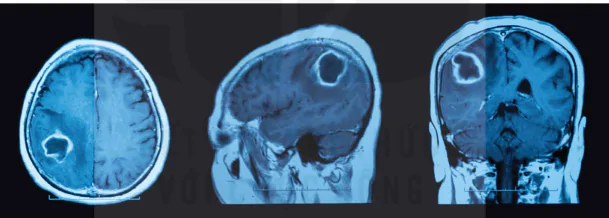

Ví dụ: Nước và các mô chứa nước (ví dụ như dịch não tuỷ) có thời gian hồi phục dài trong vài gây, các mô mỡ (ví dụ như chất trắng trong não) có thời gian hồi phục ngắn hơn cỡ vài trăm miligiây, các mô ung thư có thời gian hồi phục nằm ở khoảng giữa hai thời gian hồi phục của hai chất này.

Hình 8.3. Hình ảnh chụp cộng hưởng từ u não

Các bộ phận trong cơ thể người được cấu tạo bởi các mô khác nhau, do đó thời gian hồi phục với từng vị trí trong cơ thể cũng khác nhau. Máy tính sẽ phân tích dữ liệu thời gian hồi phục ở từng vị trí trên cơ thể để dựng thành hình ảnh gọi là ảnh cộng hưởng từ hạt nhân.